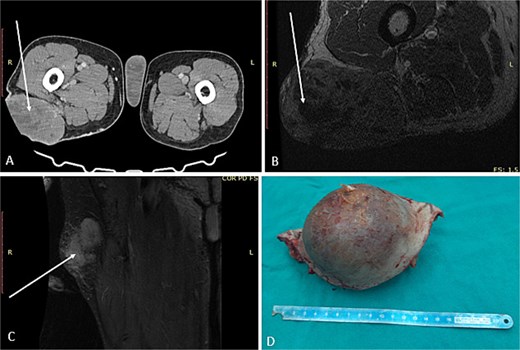

А 68-year-old male presented at the University Clinic for Orthopedic Surgery with a soft tissue mass at the right femoral region. After detailed clinical and radiological investigations, the tumor board decided that a wide resection was most beneficial (Fig. 1A–C). Grossly the tumor measured 10 × 8.6 × 7.5 cm, white to tan colored tumor tissue with a soft consistency and large areas of necrosis and hemorrhage, surrounded with a pseudocapsule. The tumor was covered with intact and elevated skin (Fig. 1D). Microscopy revealed a highly cellular tumor composed of elongated, spindle cells in a “herringbone” arrangement with collagen deposition between cells. Large areas of hemorrhage and necrosis were confirmed. The tumor cells were negative for S-100, desmin, and smooth muscle actin (SMA), while positive for vimentin. A diagnosis of fibrosarcoma was made, and according to UICC, 8th edition the disease was in the IIIB stage. After the surgical treatment, the patient refused the course of adjuvant chemotherapy, and 2 years later the patient presented again with a large soft tissue mass in the left gluteal region confirmed as metastasis.

First surgical treatment. (A) CT, (B and C) MRI, (D) surgical specimen.